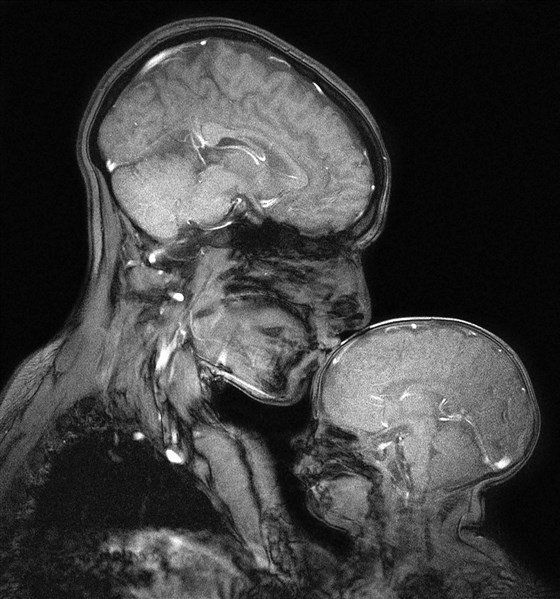

My brain is just saying ‘nope’ whenever I need it to do something for me and my head feels heavy and sore. I haven’t smiled properly in forever and I’m missing the manic me. It’s been depressed me for so long.